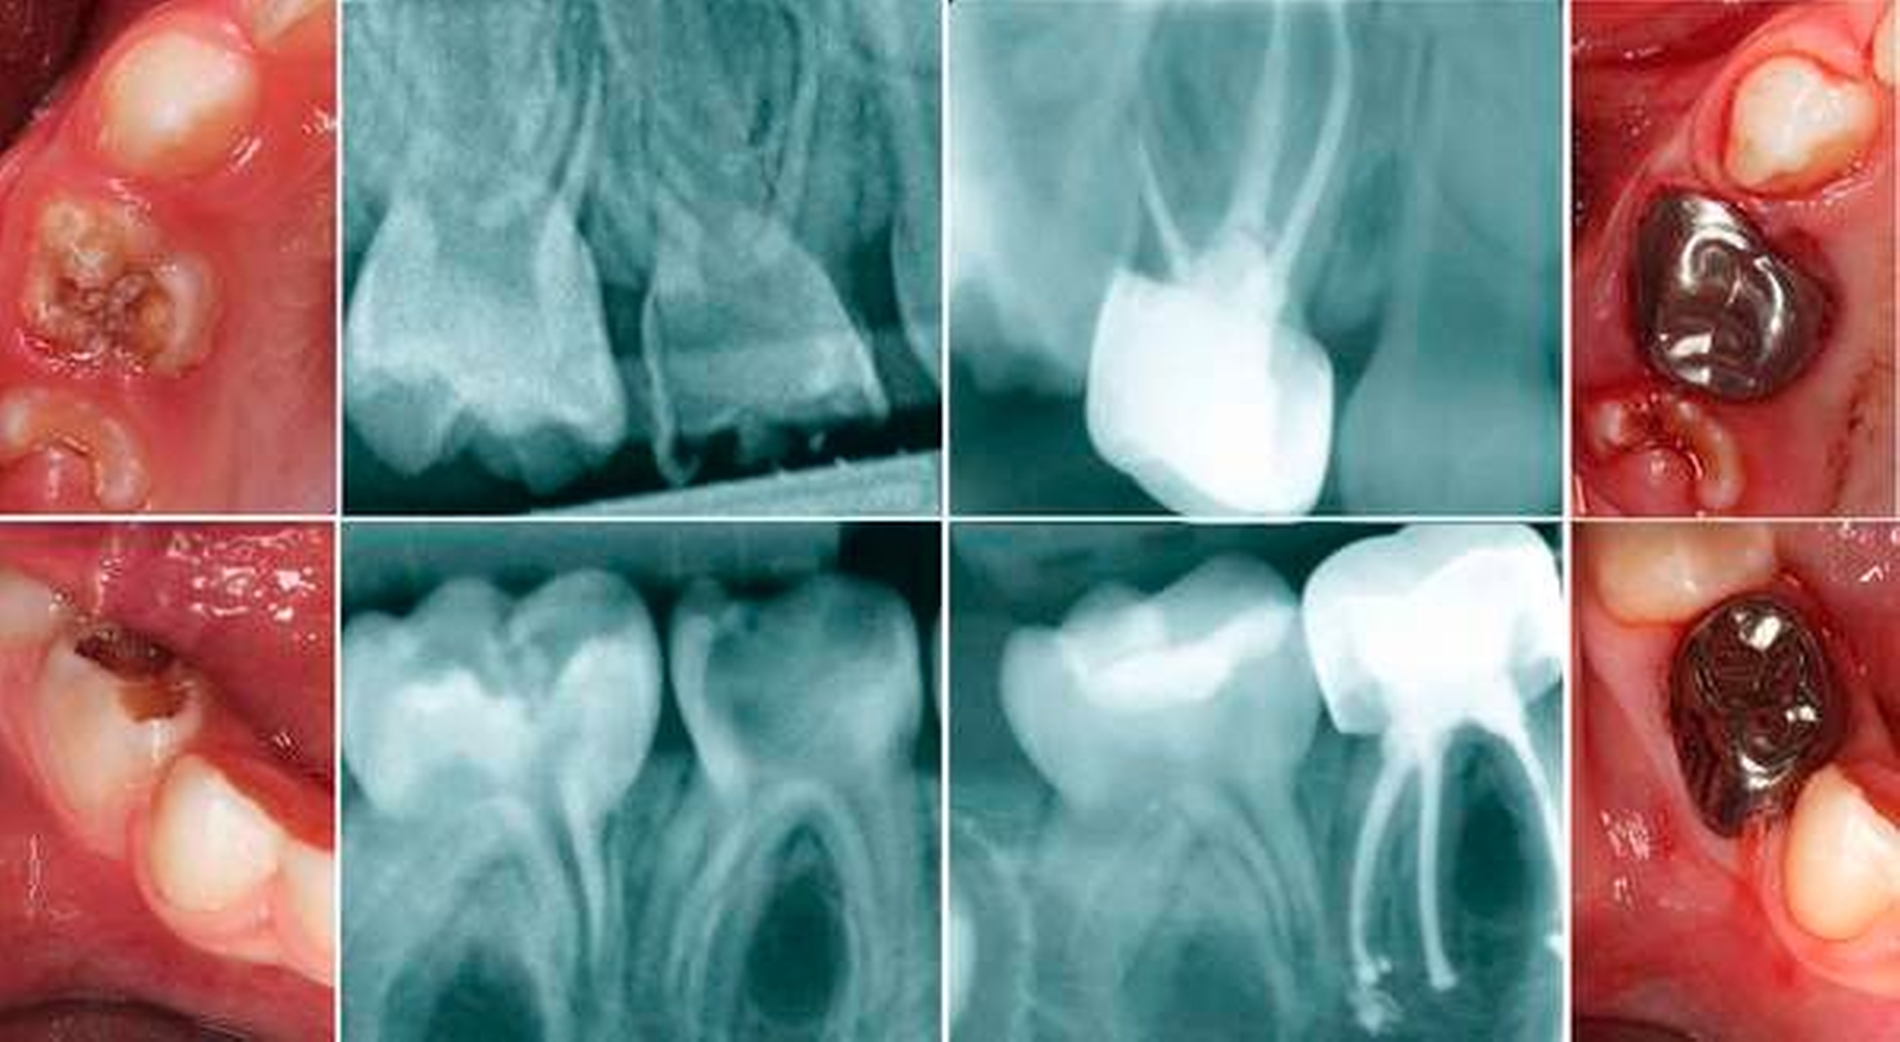

Wenn bereits Schmerzen oder eine umfangreiche Zerstörung an einem Zahn vorliegen, muss ein Zahnfilm angefertigt werden, um das mittlere Wurzeldrittel beziehungsweise die interradikuläre Zone beurteilen zu können. Der dünne Pulpaboden besitzt viele akzessorische Kanäle, so dass sich eine Pulpitis nicht wie bei einem bleibenden Zahn periapikal, sondern meistens interradikulär im Sinne einer Osteolyse im Bereich der Bi- oder Trifurkation darstellt [Waterhouse et al., 2011; Van Waes und Steffen, 2009].

Bevor eine Wurzelkanalbehandlung am Milchzahn mit einer irreversiblen Pulpitis geplant wird, sollte ebenfalls eine klinische (keine Mobilität, keine Schwellung/Rötung oder Fistel) und röntgenologische Diagnostik (mindestens zwei Drittel der Wurzel vorhanden, keine interradikuläre Aufhellung, keine interne oder externe Resorption) erfolgen. Ferner sollte die Mitarbeit des Kindes geprüft und die Wirtschaftlichkeit der Therapie abgewogen werden. Die Wurzelfüllung am Milchzahn erfordert erneut ein Umdenken, da keine Verlängerung der Wurzelkanäle erwünscht wird und ein Überinstrumentieren zum Schutz des Zahnkeims unbedingt vermieden werden muss.

Die Aufbereitung dient der Entfernung der Bakterien und des infizierten Pulpagewebes. Ein großflächiger Abtrag von infiziertem Dentin ist hingegen nicht gewünscht. Zudem sind bei jungen Kindern die Kanalwände sehr dünn, so dass eine forcierte mechanische Kanalreinigung Perforationen hervorrufen kann. Zur chemischen Aufbereitung haben sich Natriumhypochlorid aufgrund seiner gewebsauflösenden und antibakteriellen Eigenschaften sowie Kochsalz als Abschlussspülung bewährt. Nach Trocknung des Kanalsystems mit Papierspitzen wird im Idealfall eine resorbierbare Kalziumhydroxid-Jodoform-Paste (zum Beispiel Vitapex, Neo Dental International Inc, Kanada) mit leichtem Druck eingebracht und der Zahn nach Anfertigung eines Röntgenkontrollbilds mit einer Krone versorgt [AAPD, 2017]. Die Wurzelfüllung des Michzahns wird zumeist zum Erhalt der Oberkieferfrontzähne durchgeführt (Abbildung 8). Aber auch im Seitenzahnbereich ist dieser Eingriff sinnvoll, vor allem bei sehr jungen Kindern, bei denen ein frühzeitiger Zahnverlust vermieden werden soll (Abbildung 9).